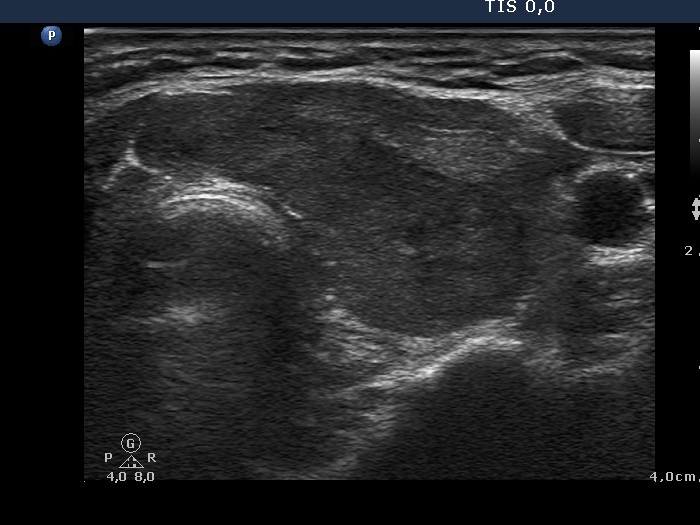

Clinical data: a 52-year-old hypothyroid woman was referred for an evaluation of a nodule detected by an ultrasound examination.

Ultrasonography: the thyroids were moderately hypoechogenic. The dorsal 4/5 of the left lobe was more hypoechogenic. This hypoechogenic area could be followed all along the dorsal part of the left lobe and the isthmus.

Comment: the shape of a nodule is egg- or ball-shaped. A pipe-shaped formation like a vessel or muscle fiber or as in this case a large area of the thyroid with different echo structures may mimic a nodule. But in the latter cases if we put the transducer in line with the formation we can notice the pipe-like shape. Conversely, if we put the transducer in other angles, first of all perpendicular to the object then it seems to be a nodule.